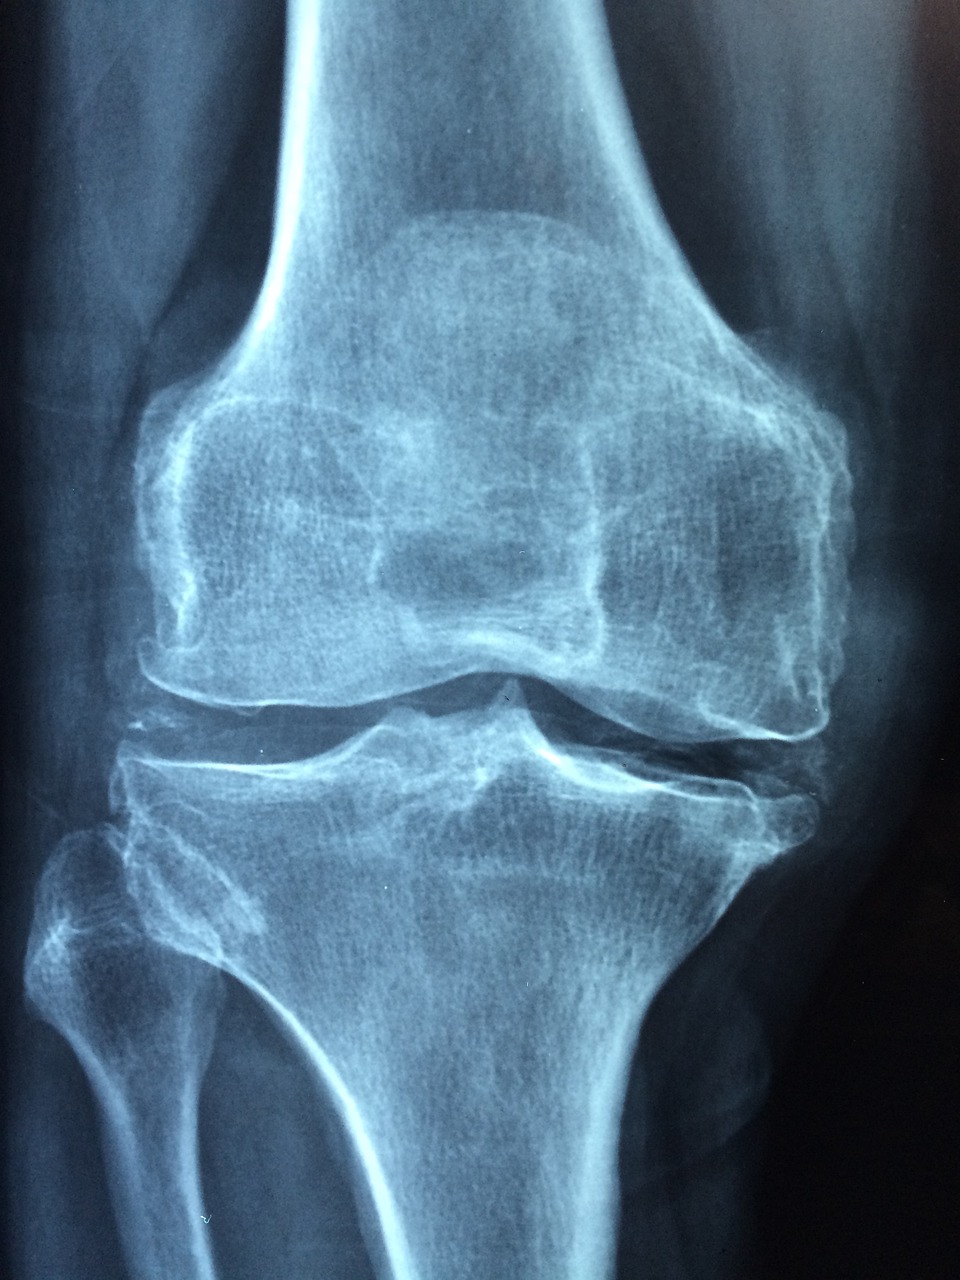

무릎 연골 수술 비용이 궁금하신가요?

무릎이 자꾸 시큰거리고 걷는 게 불편하다면, 혹시 연골 문제는 아닐까요?

1️⃣ 무릎 반월판 연골 수술 (단측) 비용과 입원일수

단측 수술은 한 쪽 무릎만 수술하는 방식으로, 비교적 빠른 회복과 짧은 입원 기간이 특징이에요. 평균적으로는 약 5일 정도 입원하게 되며, 비용은 병원마다 차이가 있어요.